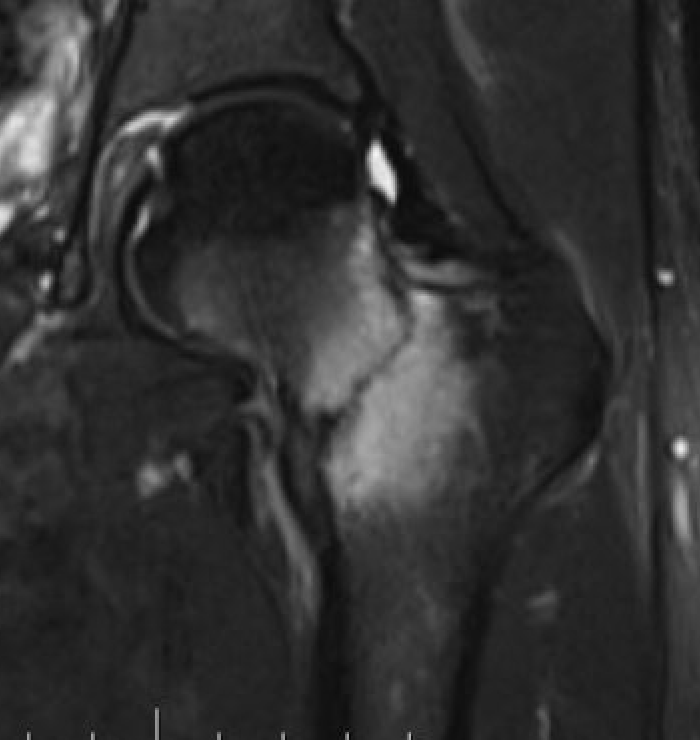

MRI

Edema / fracture line / hip effusion

MRI demonstrating edema likely across entire neck

MRI demonstrates complete fracture